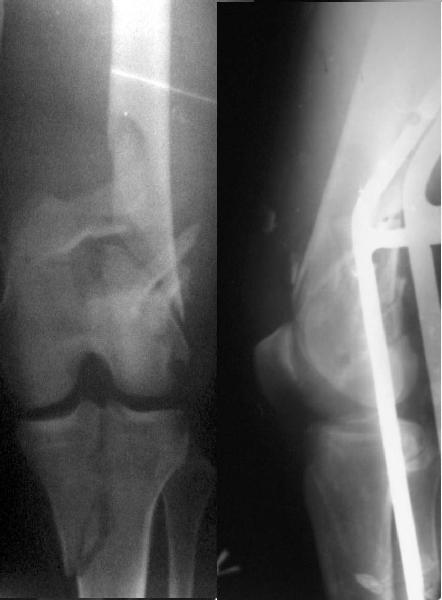

This is what we have done... As generally true for LISS look at the bone not the hardware.

There are two more srews above. The one not completely in got damaged head.

A. Knee stiffness

B. If the gap left as wide as it is on the post op x ray it may led to Non union.